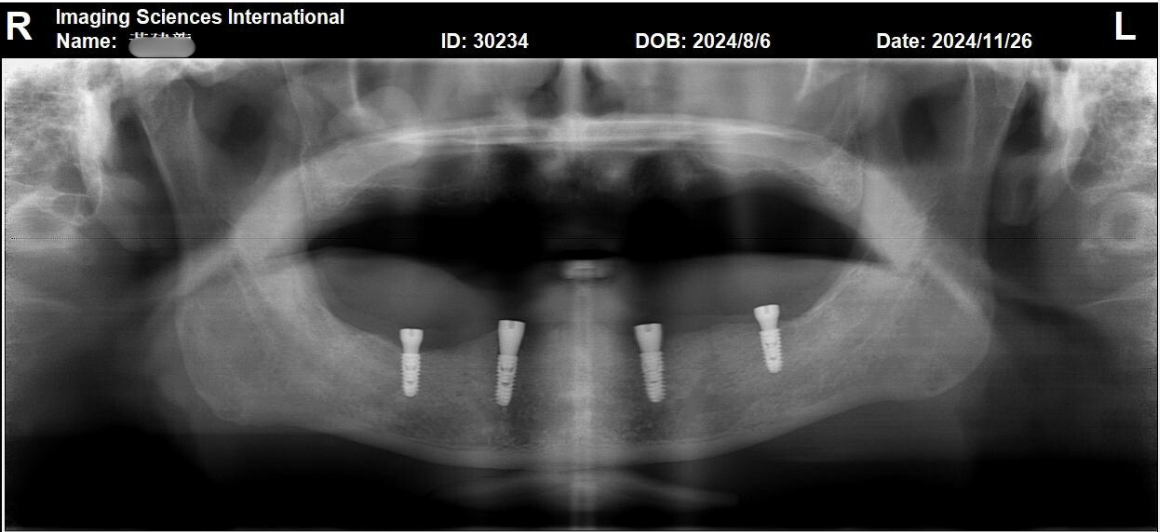

張正忠醫師先替患者進行All-on-4數位植牙手術,透過數位手術導板,在他的下顎前牙與小臼齒區段,均勻植入4支植體(如下圖),其中的後側兩支植體,採傾斜植入,增加力學支點寬度,減少補骨需求。

等到植體與齒槽骨完美密合後,醫師便為患者進行支臺齒安裝。從影像顯示(如下圖)能發現,植體周圍骨質已呈現穩定的狀態,可為後續的全口重建打下堅實基礎。